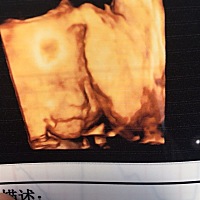

帮我看一下 这个月还有戏吗